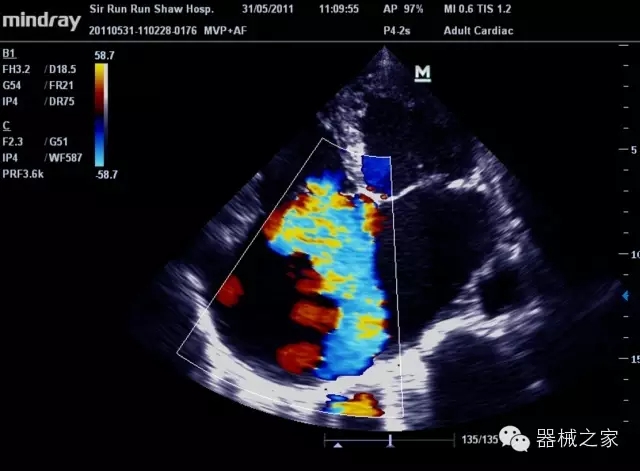

經(jīng)典產(chǎn)品:M7(星鉆)

臨床圖片賞析

產(chǎn)品特點(diǎn)